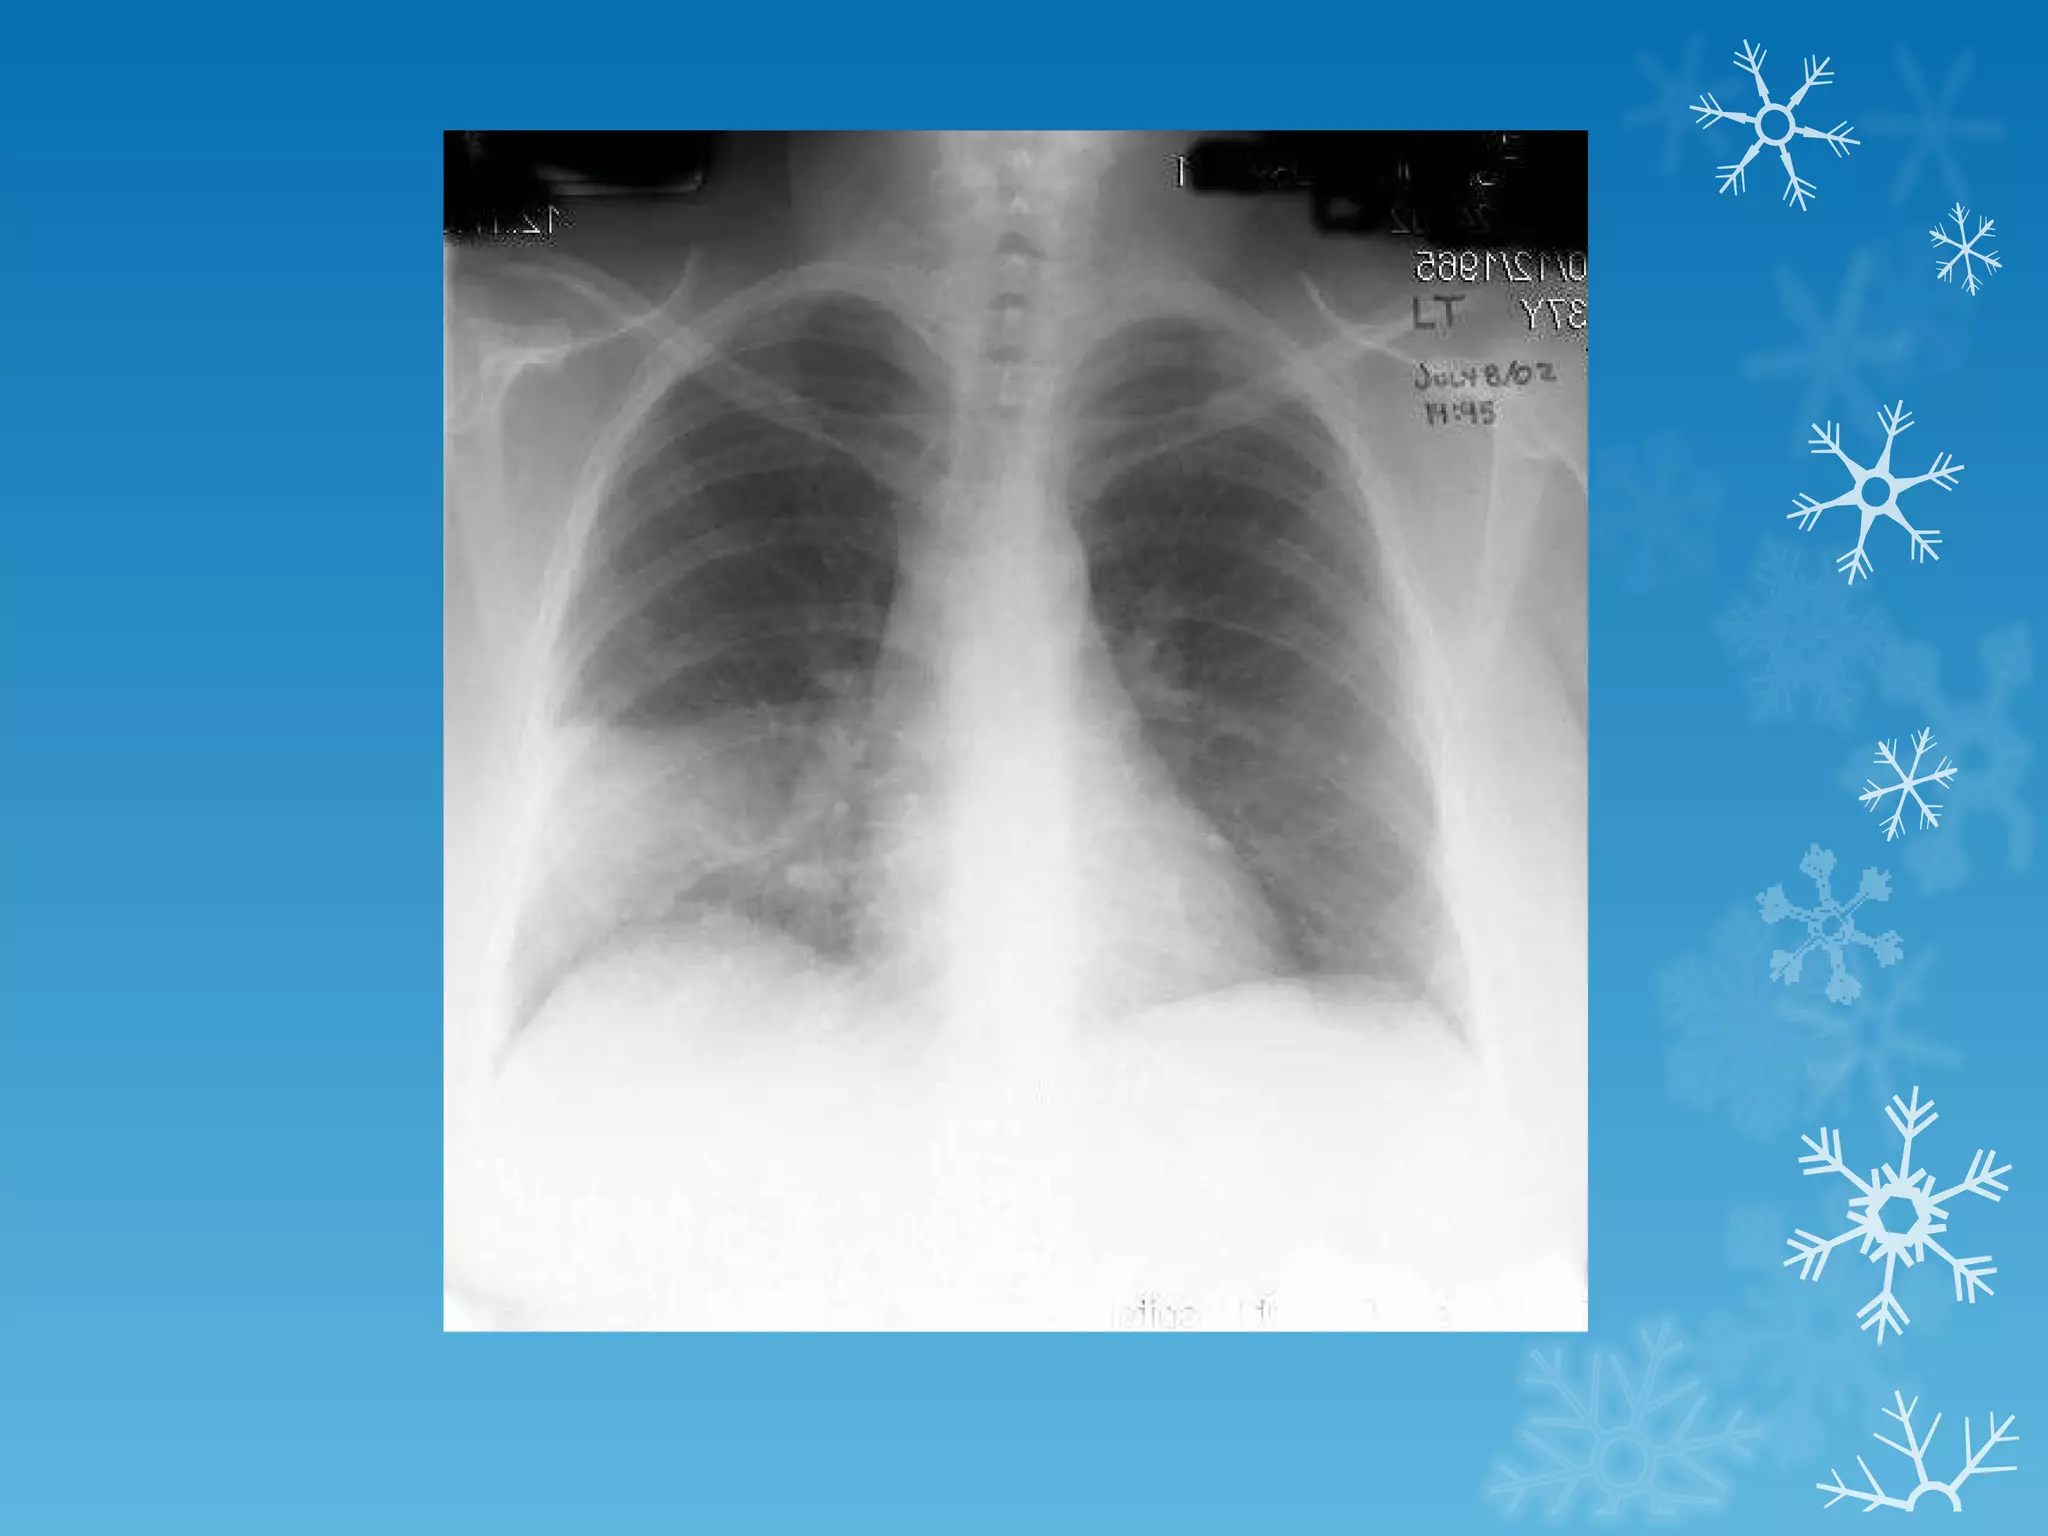

This document discusses chest x-ray interpretation and provides guidance on evaluating x-rays. It explains that tissue density determines how an x-ray beam penetrates, with denser tissues appearing whiter and less dense tissues appearing blacker. It also outlines different chest x-ray views and factors to consider like patient orientation, age, gender, and rotation. Abnormalities are described as appearing too white, too black, too large, or in the wrong place. The document stresses a systematic approach of identifying, localizing, describing lesions, and providing differential diagnoses.